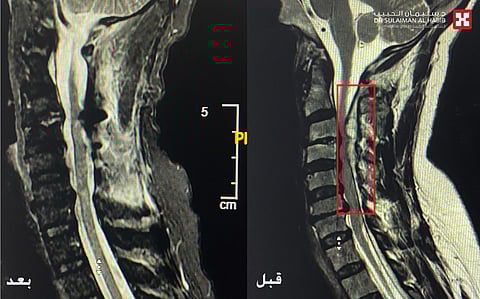

مفيداً بأنه تم تقديم الإسعافات الأولية له، ومن ثم تحويله إلى العناية المركزة، وإخضاعه لفحوصات دقيقة بأشعة الرنين المغناطيسي (M.R.I)، ومجموعة من التحاليل المخبرية. وقد كشفت نتائج الفحوصات عن وجود نزيف بالأوعية الدموية وورم ضاغط على الحبل الشوكي، بالفقرات الأولى حتى الرابعة العنقية.

وأضاف د.هاني أنه بعد دراسة كافة نتائج الفحوصات ومناقشة التفاصيل، تم اتخاذ القرار بإجراء عملية جراحية عاجلة، عبر تخدير نوعي في مدة لا تتجاوز 4 ساعات، للحد من المضاعفات الخطيرة التي قد يتعرض لها المريض، خاصة وأنه يعاني من تاريخ مرضي، يشمل إصابته بالأمراض القلبية ومشاكل حادة الكلى. وبعد اتخاذ كافة التدابير اللازمة تم إجراء جراحة دقيقة استغرقت 6 ساعات، استخدم فيها جهاز مراقبة الأعصاب أثناء العملية، وتقنيات الميكروسكوب المتطور، حيث تم عمل فتحة بمنطقة الرقبة وصولاً لمكان الورم بالفقرات العنقية، وتحرير الورم من التصاقاته واستئصاله بالكامل، ومن ثم فك الضغط على الأعصاب، وكذلك معالجة تشوه الشرايين الدماغية.